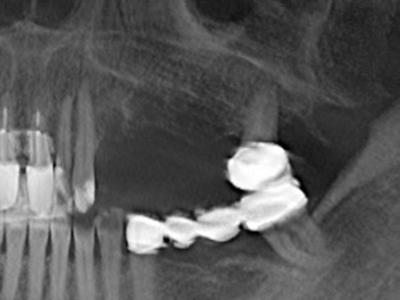

En la extracción de bloques óseos la piezocirugía también presenta ventajas adicionales: Además de la alta precisión en la osteotomía que ya se ha descrito antes, se ha comprobado que el uso de los delgados insertos de sierra resulta especialmente cuidadosas con el hueso. Frente a esto, sobre todo cuando se usan las fresas de Lindemann, cabe esperar pérdidas en la extracción significativamente más altas debido al mayor grosor de la parte frontal del cabezal (Lakshmiganthan, Gokulanathan et al. 2012). La separación basal que se necesita en particular en los injertos de bloque extraídos de forma retromolar se ve facilitada mediante sierras perpendiculares especialmente previstas a tal fin, lo que permite considerar que la cirugía piezoeléctrica es un procedimiento preciso y seguro para la obtención de bloques de hueso en el área retromolar (Happe 2007) (fig. 1-12).